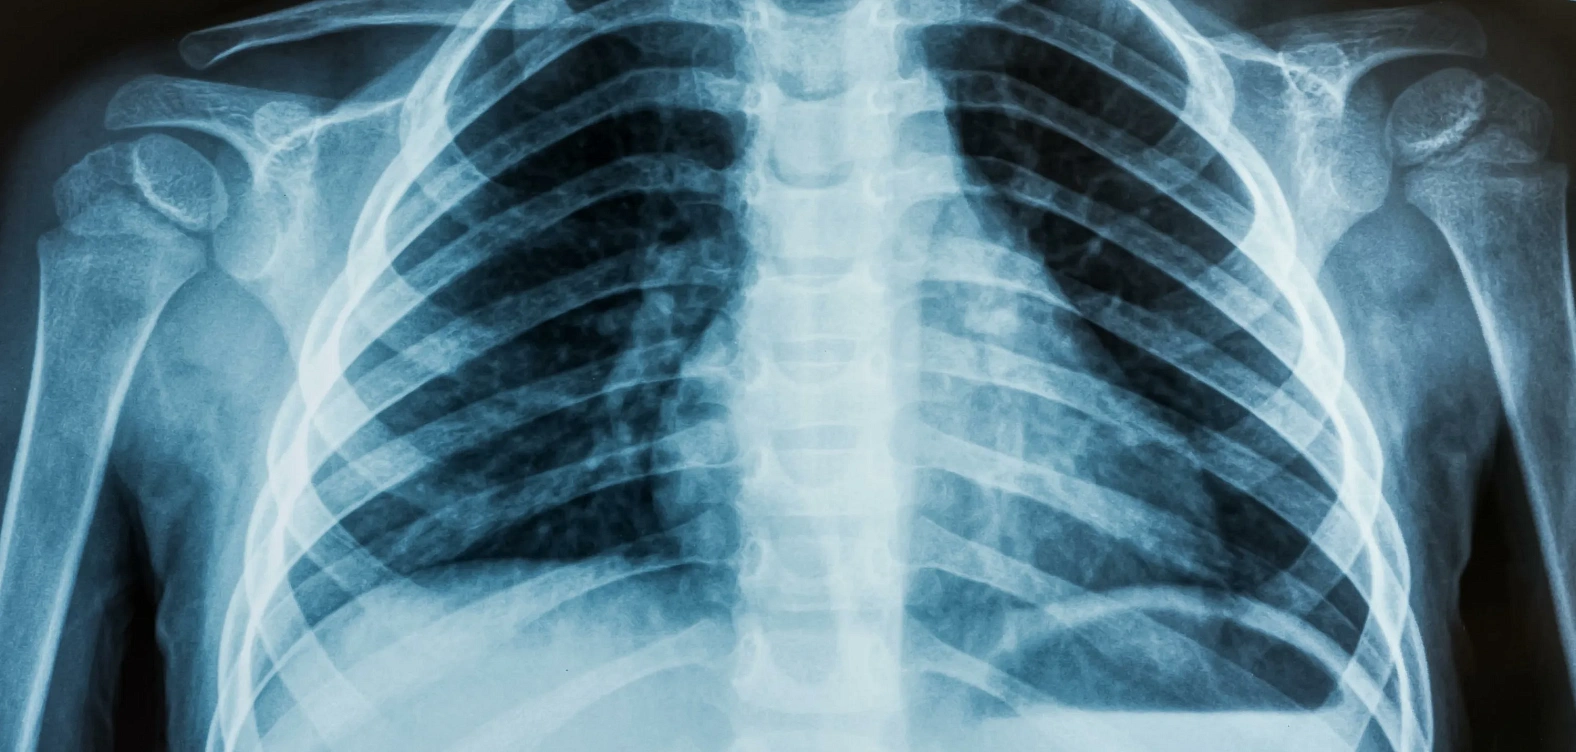

Рентен органов грудной клетки

Рентгенография грудной клетки — это неинвазивное исследование, при котором с помощью рентгеновского излучения получают изображения внутренних органов. Этот метод широко используется для диагностики заболеваний дыхательной системы, сердца и крупных сосудов, а также для оценки состояния рёбер и позвоночника.